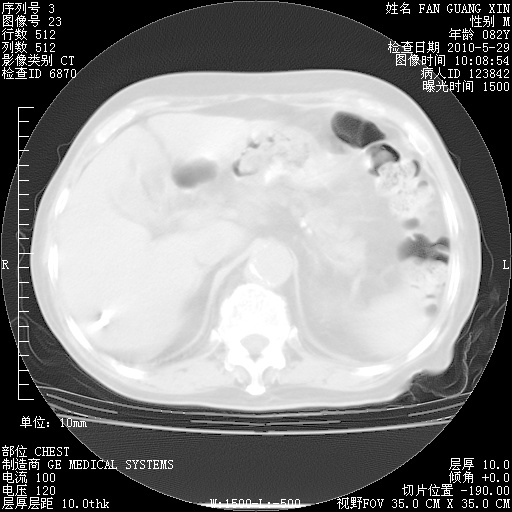

再治疗10天后的肺部CT

再治疗10天后的肺部CT 纵膈窗

阅读此次胸部CT,肺间质渗出性改变较入院时有吸收。目前从体温、白细胞、中性分叶明显增高,肯定存在细菌感染(发生医院感染哦,若无消化道及泌尿系统等感染的依据,肺部感染可能大)。若你院头孢哌酮舒巴坦钠耐药率较高,同意你的方案,若48小时体温仍高,可考虑使用碳青霉稀类抗菌药物,同时可予超声雾化、注意滴数时加大液体量。白蛋白33.30g/L较低哦,需加强营养等支持治疗。